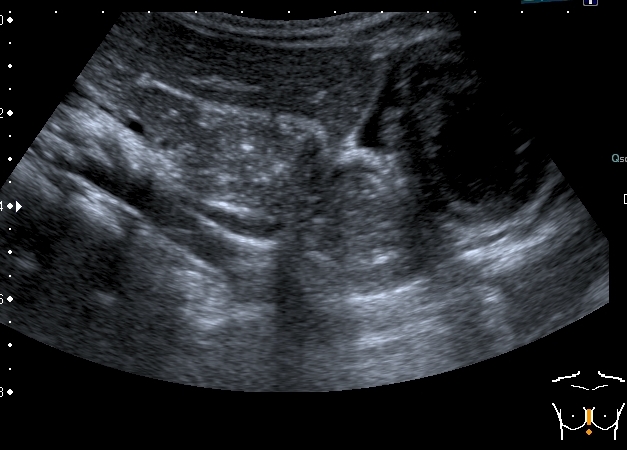

Девочка 4-х лет, жалобы на длительный кашель (оеоло 1-го месяца). В поликлинике выполнена рентгенография органов грудной клетки, выявлены изменения (какие - пока не скажу). Госпитализирована. Направлена на УЗИ сердца. При УЗИ - в самом сердце - патологии не выявлено, но позади него к правому предсердию прилежит полостное образование с акустически неоднородным содержимым.

Анализы крови - не изменены, температуры - нет. Девочка чувствует себя хорошо. Небольшая подсказка: я перешёл с секторального кардиологического датчика на абдоминальный...Serg

Сканы через пищеводное отверстие диафрагмы